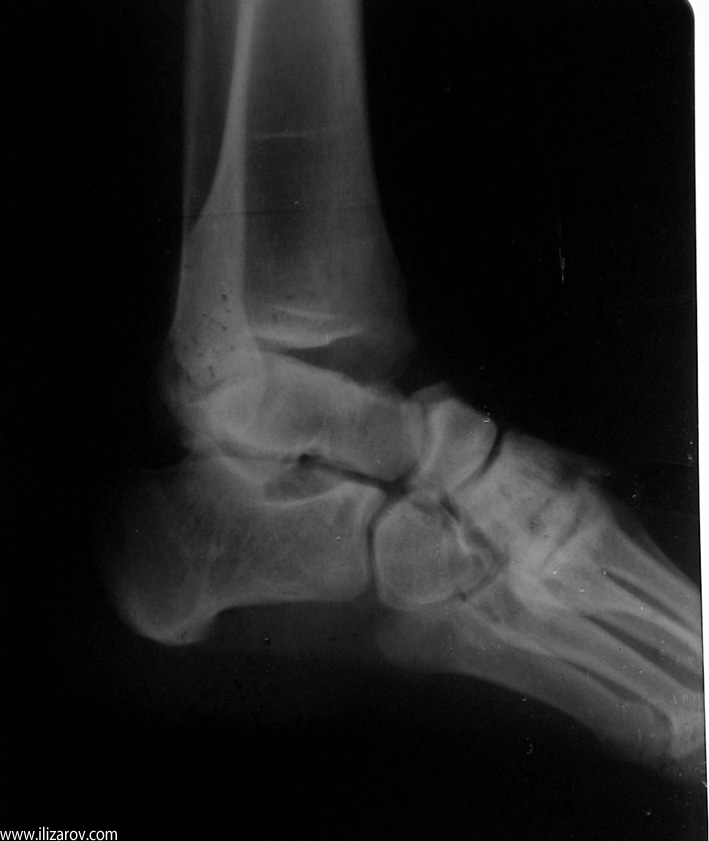

Complex foot deformities can ocur after trauma, neglected or relapsed clubfoot, poliomyelitis, osteomyelitis, burn contracture, neuromuscular diseaes and similar disorders. When treating this deformity with wide soft tissue releases, osteotomies and arthrodesis, there are disadvantages such as the risk of neurovascular injury, soft tissue problems and shortening of the foot. Besides, treating previously operated cases is even harder.

The aim of treatment in foot deformities is to acquire painless and fuctional foot which is plantigrade and at normal size. With the Ilizarov method, correction is planned in 3 planes and performed at a rate depending on the type and degree of the deformity. The deformity is corrected without shortening of the foot, with minimal surgical morbidity and the rate and direction of correction is controlled by the surgeon.

Using the Ilizarov method, foot deformities can be corrected either with or without osteotomy. The system without osteotomy corrects deformities through joints. This technique can be used in patients smaller than 8 years of age and without fixed bony deformity. For patients older than 8 years of age with fixed bony deformity and patients with neuromuscular diseases, in whom maintaining soft tissue correction is very hard, osteotomy is required.